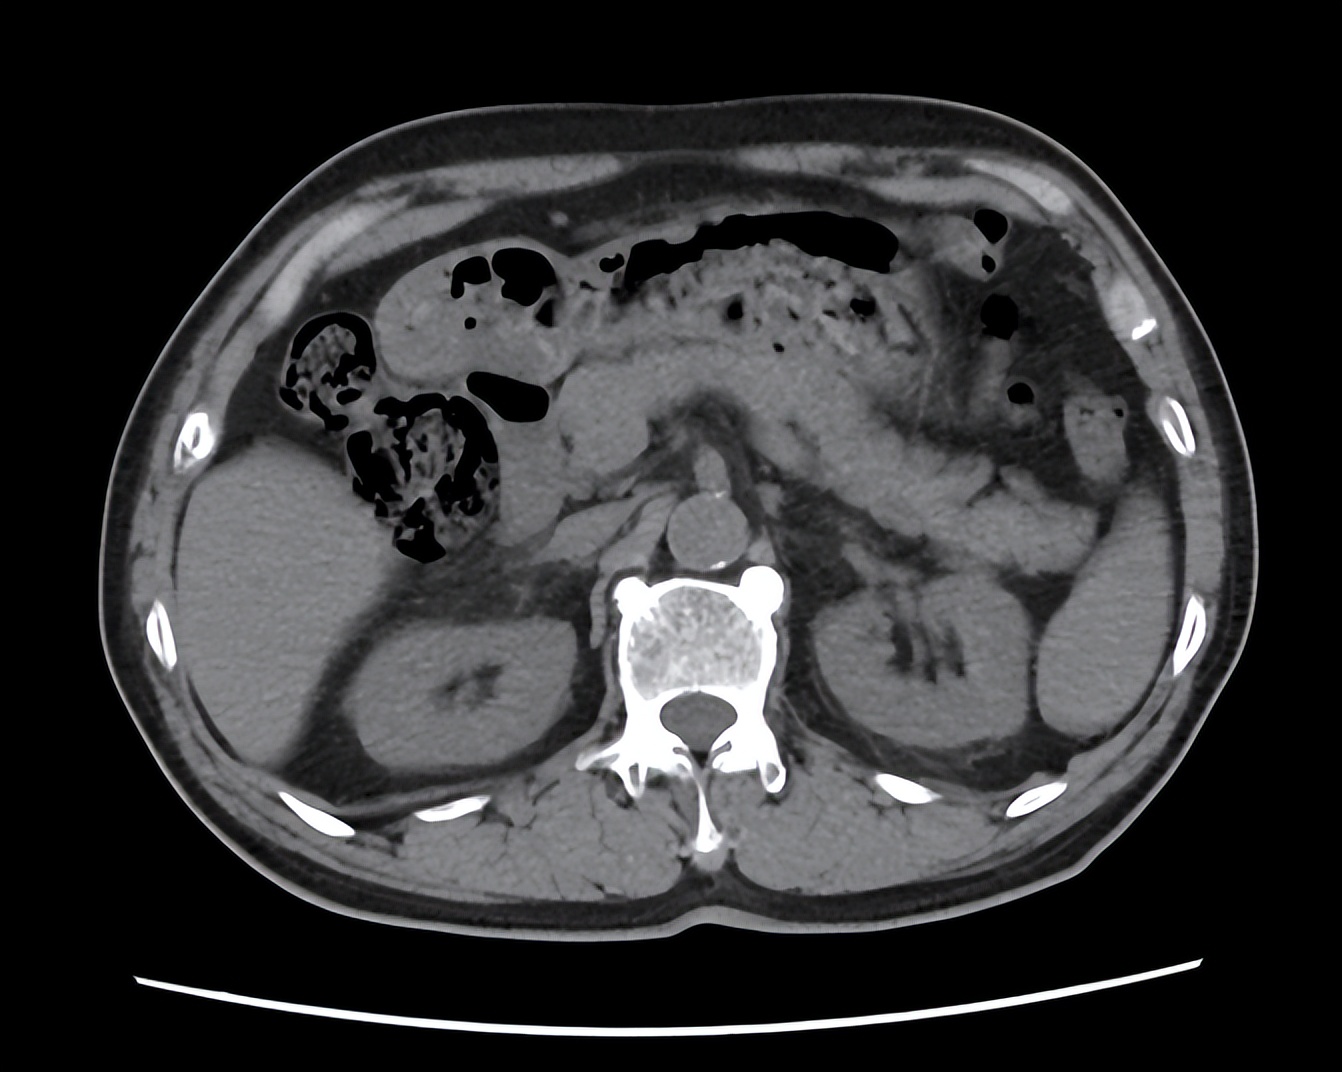

这可把张女士吓坏了,赶紧来到医院就诊,我给张女士做了体格检查,发现左侧肾区叩击痛明显,怀疑是急性肾盂肾炎,便先安排了尿常规和尿路CT检查。尿常规显示尿白细胞3+,尿红细胞2+,尿路CT显示左肾周渗出明显。张女士确诊为急性肾盂肾炎。